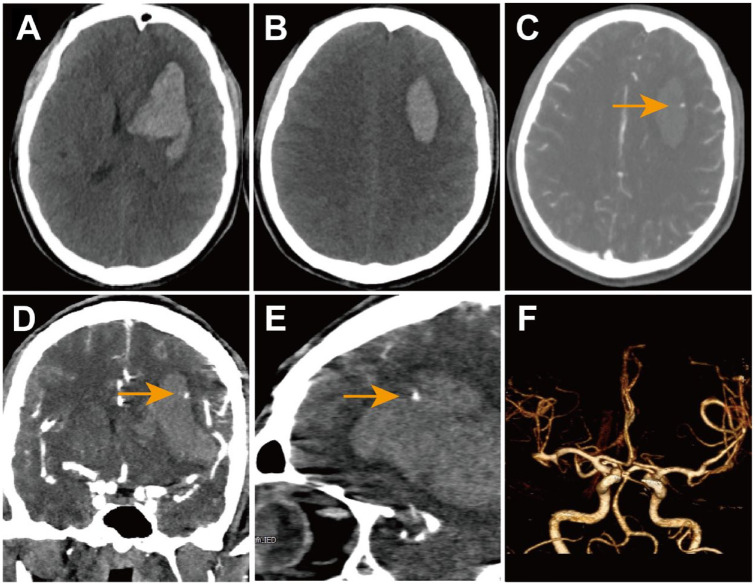

Case presentation: A 48-year-old man presented with a 9-hour history of alalia and right limb hemiplegia. Noncontrast computed tomography (CT) revealed a hematoma in the left frontal lobe, while CTA showed a spot sign within the hematoma, leading to a diagnosis of frontal lobe hemorrhage. During the surgical procedure, a blood clot was removed, revealing the presence of 3 mm of saccular tissue resembling an aneurysm. The process of exposing its complete form resulted in its rupture and bleeding. The location of this tissue at the top of the hematoma cavity corresponded to the CTA spot sign. Pathological examination confirmed that the characteristics of the tissue wall were consistent with those of a pseudoaneurysm.

Conclusion: This case suggests that more stringent identification criteria should be established in studies predicting ICH expansion using the spot sign on CTA to differentiate and exclude pseudoaneurysms, thereby improving the accuracy of predicting early hematoma expansion using the CTA spot sign.